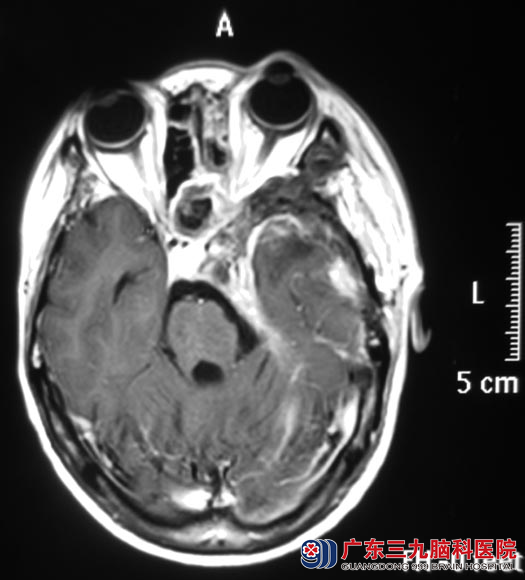

吴女士2年前出现左侧颜面部麻木感、如蚂蚁爬行感;一周前突然出现视物重影,伴头痛头晕,当地医院头颅CT显示:左侧中后颅窝巨大占位。广东三九脑科医院头颅MR检查提示:左侧中、后颅窝颅内外区示一巨大占位病灶,大小约77.5mm×70.8mm×45.2mm,累及左侧颞下窝及翼腭窝、左侧颞部,向前向下突入上颌窦内,向内突入蝶鞍、蝶窦、筛窦内,左侧眶尖受累,向后突破岩尖伸入后颅窝左侧桥小脑角区,邻近脑干明显受压变形、移位,四脑室变形、稍变窄。CT提示相应骨质呈膨胀性的吸收破坏。

术后吴女士左侧颜面部麻木感消失,头痛、头晕症状明显好转。术后病理结果为:神经鞘膜瘤。